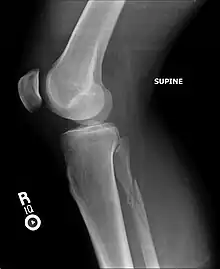

Maisonneuve fracture

| A Maisonneuve fracture with arrows marking the location of the two fractures | |

A Maisonneuve fracture is an injury at the ankle with an associated break of the lower leg near the knee.[5] The ankle injury involves a tear of the ligament connecting the two bones of the lower leg, the tibiofibular syndesmosis.[5] There may also be a break of the medial malleolus or rupture of the deltoid ligament of the ankle.[3] Symptoms typically include tenderness over the medial ankle and outside aspect of the upper part of the lower leg.[1]

It typically results from excessive external rotation of the ankle.[3] X-rays typically show widening of the ankle joint, though this may be subtle.[3][1] Stress views may be useful in unclear cases.[4] People may not mention pain around the knee due to the greater degree of pain in the ankle.[6] It is classified as a type C3 ankle fracture according to the Danis-Weber classification system.[7]